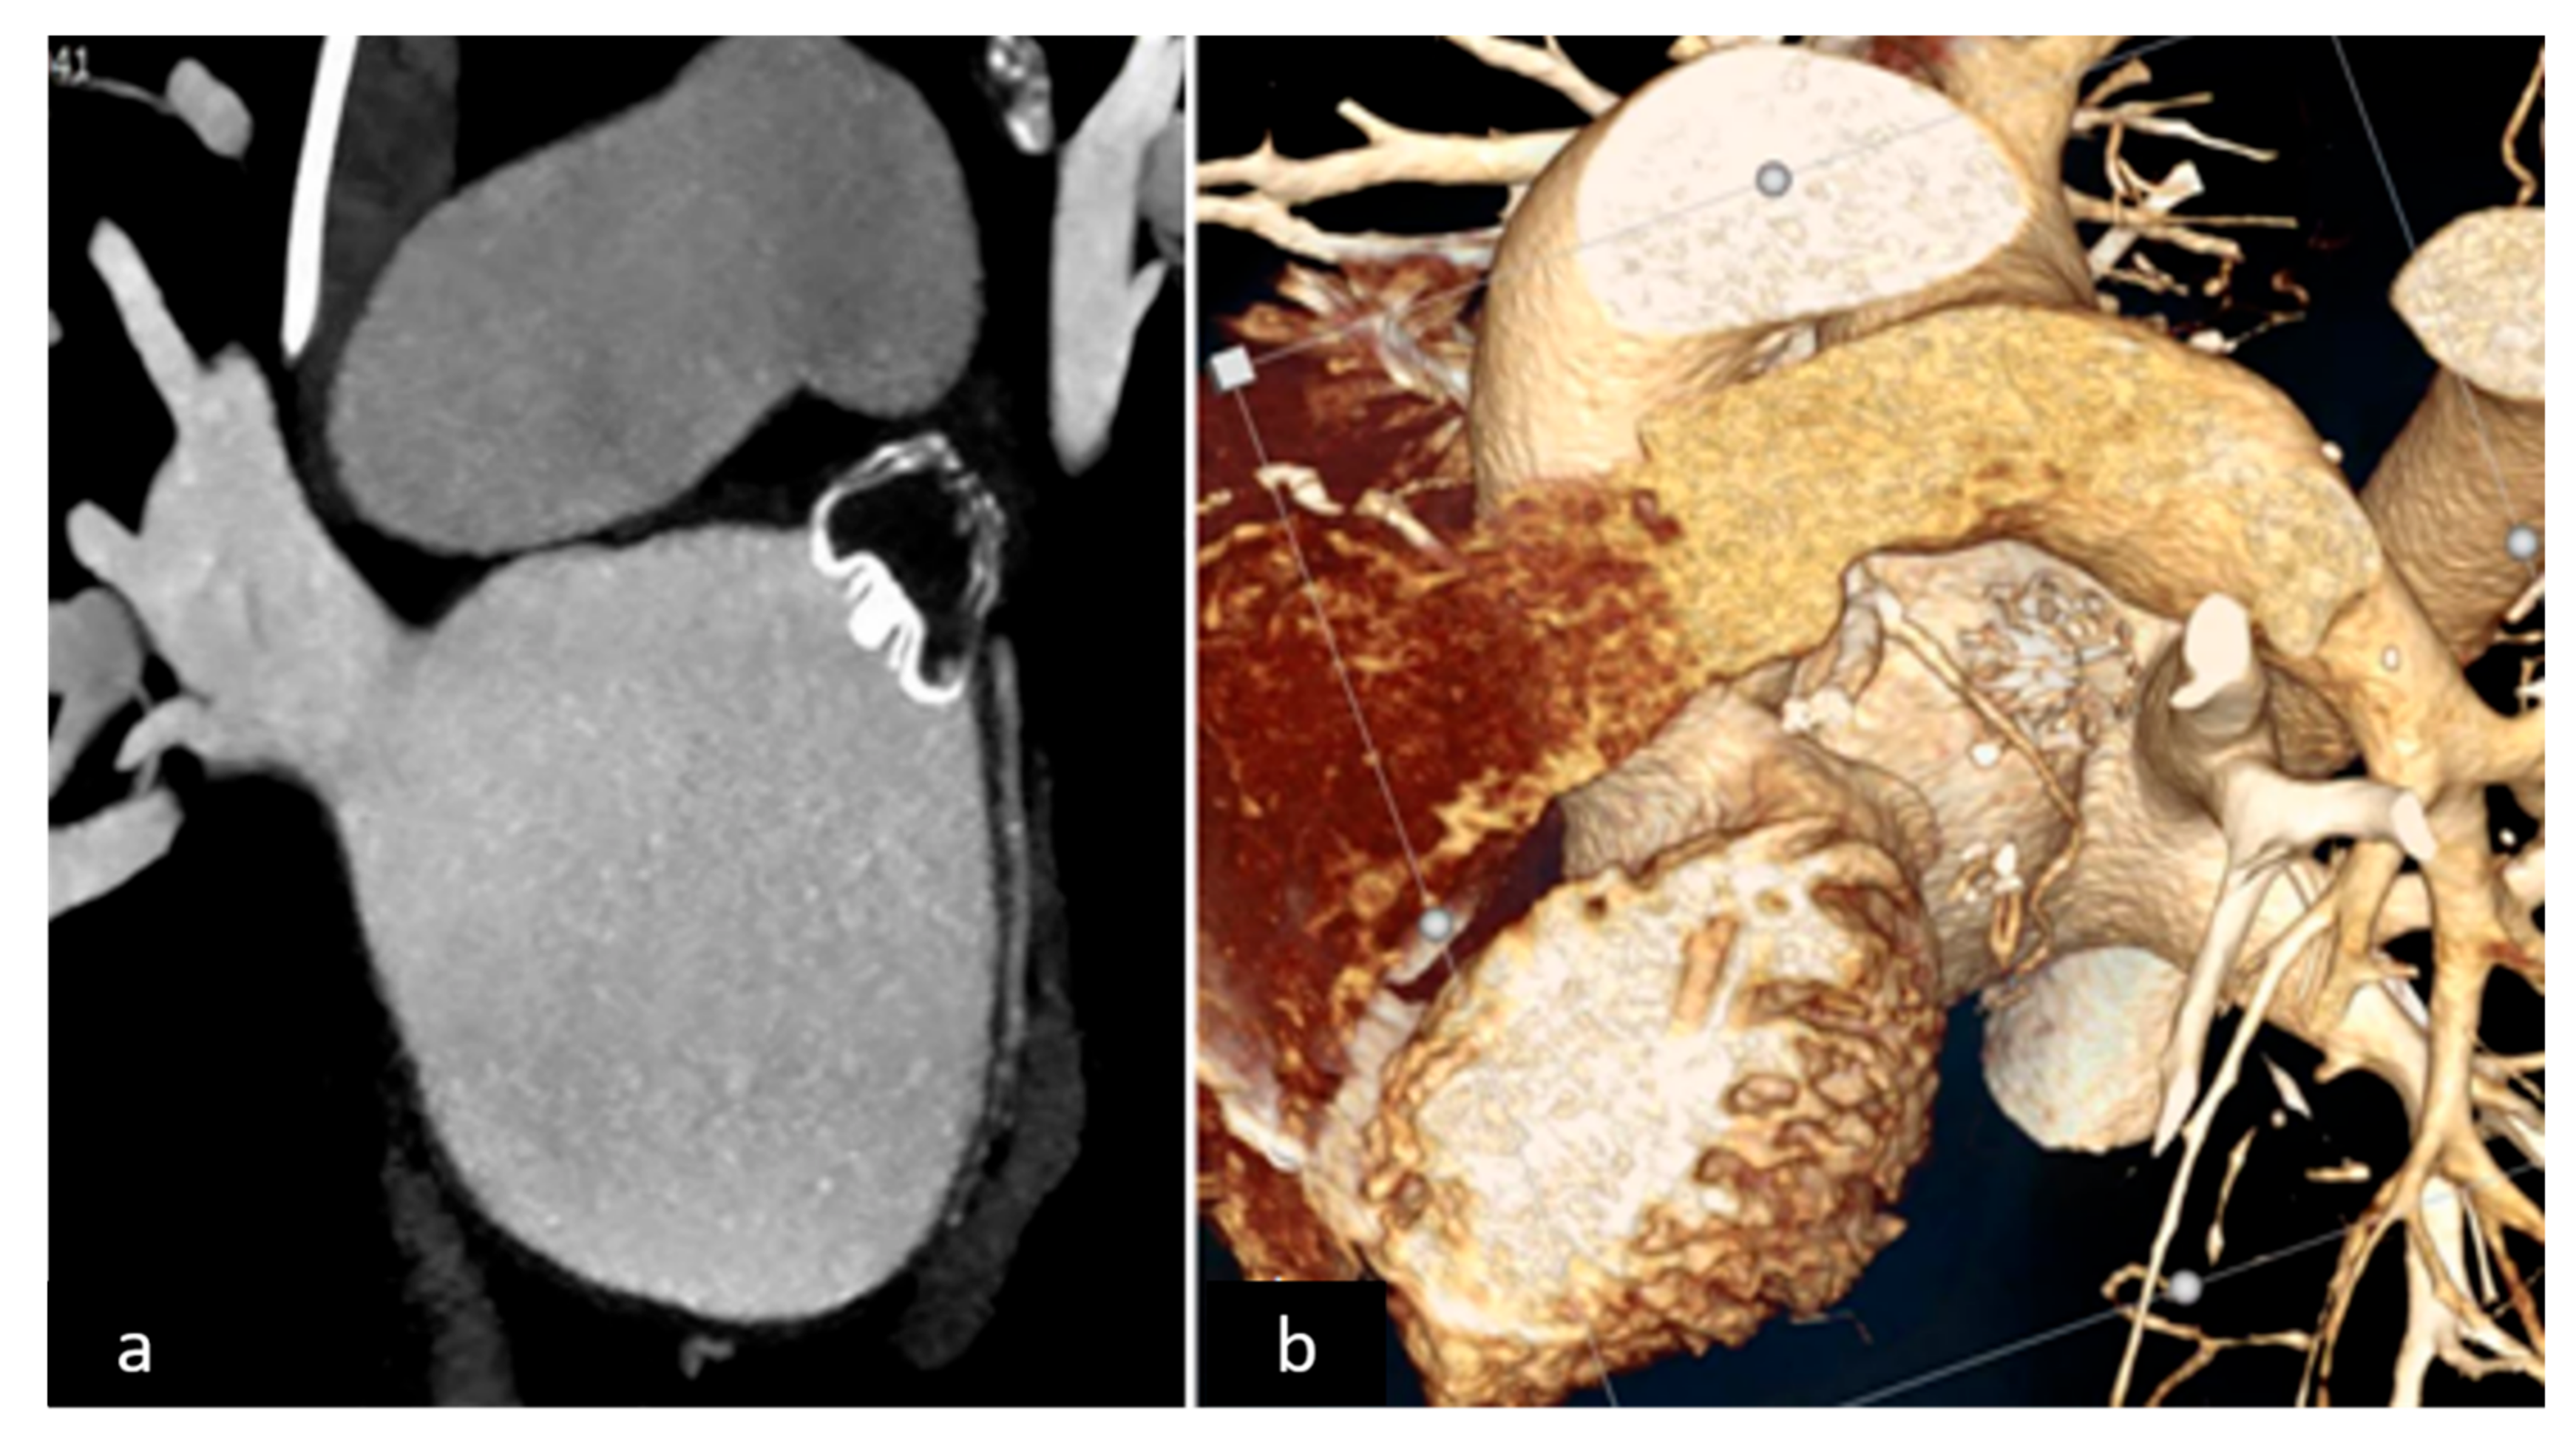

2.2. LAAO-T Procedure

2.3. LAAO-P Procedure